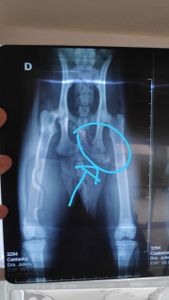

Ela quebrou dois ossos, no quadril e o fêmur... terá que passar por um procedimento cirurgico e ficar 7 dias no veterinário para recuperação. Coloquei nas fotos láudo do veterinário.